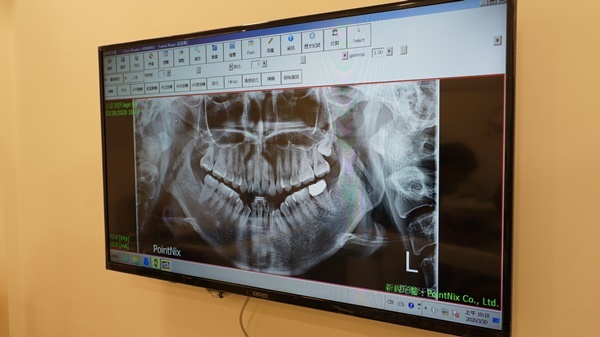

連我的蛀牙都拍得很清楚,真的滿害羞的,幸好我來之前有刷牙

做完齒模,還要拍下我矯正前的臉型以及牙齒的排列